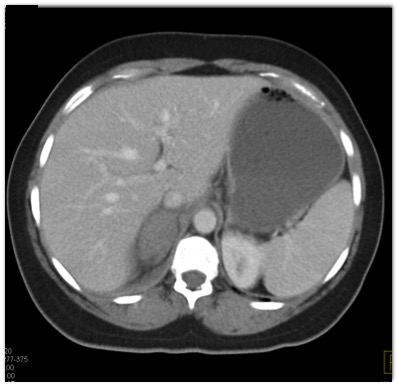

In this patient with right upper quadrant pain the most likely diagnosis is?

adrenal metastases

aldosteronoma

adrenal hemorrhage

acute hepatitis